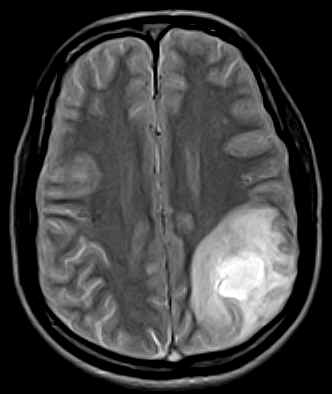

November 2005 - Venous Infarct

Diffuse hypointense areas on the T1W images which turn hyperintense on the Proton & T2W images are noted in the left parietal lobe. An area which is predominantly hypointense with a hyperintense rim on all sequences is noted in this lesion (subacute blood). The lumen of the superior sagittal sinus shows a hyperintense signal (no flow on the MRV-images not available) representative of a thrombus in this case.

On MRI:

·                     Diffuse distribution, not conforming to vascular territories (as seen with arterial infarcts).

·                     Hemorrhage may be present (20%).

·                     May find a lack of the normal flow void within a dural venous sinus (e.g. in the superior sagittal sinus).